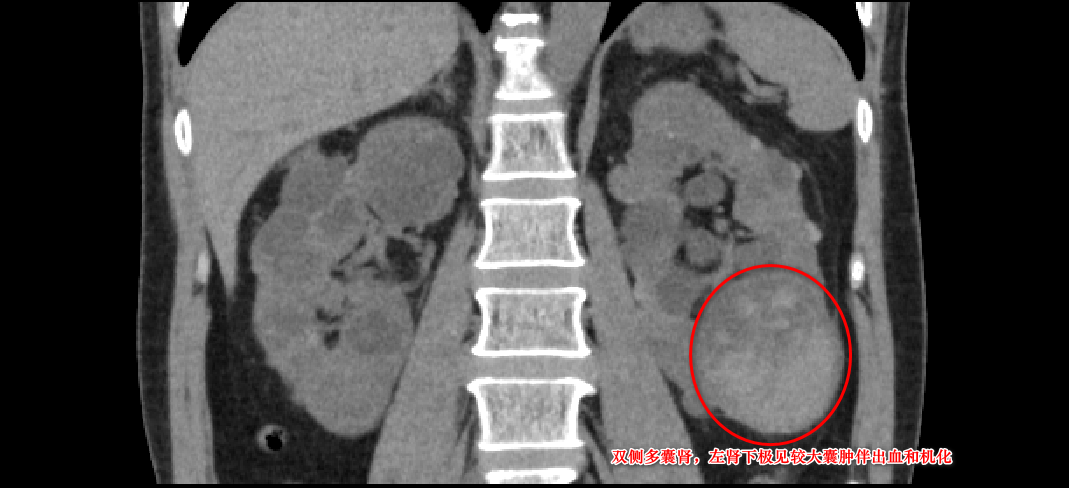

三个月前,林先生 毫无征兆出现了肉眼血尿 ,且持续多日不见好转,这才让他慌了神,急忙再次来到我院就诊。完善双肾 CT平扫提示:双侧多囊肾, 左肾较大囊肿已达7厘米。 经过对症处理病情曾好转,但入院一周前血尿再次复发,自行服药无效后,林先生决定重返医院泌尿肾病科,寻求根治。

鉴于 患者左侧肾囊肿体积较大,且存在出血和机化情况 ,若不及时治疗,不仅可能造成患侧肾脏损伤、压迫周边血管及组织,还可能导致病情进一步恶化。谢庆祥教授团队与患者及其家属充分沟通后,决定采用 创伤小、手术时间短、出血少、恢复快的腹腔镜肾囊肿去顶减压术 。